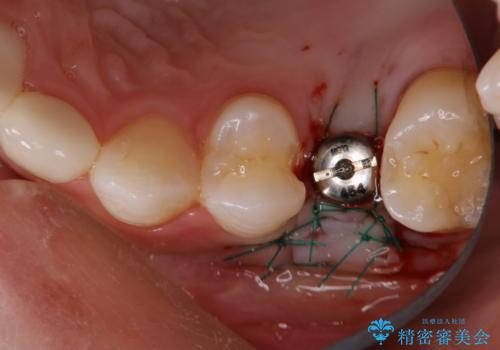

- 数年前に他医院で抜歯したままで過ごし、今回歯を入れたいとのことで来院された患者様です。

治療回数を短くしたいと1DAYインプラントを希望されました。

インプラント埋入手術は1回で全て行い、2ヶ月後にはセラミック治療で、審美回復と機能回復をしました。